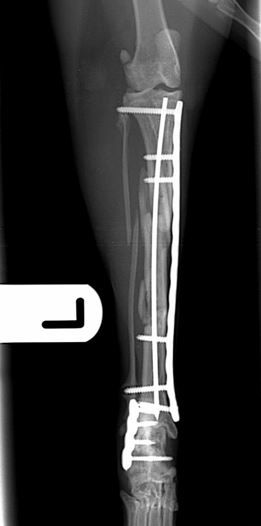

Fig. 3. Six weeks post-operative lateral and craniocaudal radiographs showing complete healing of the calcaneal fracture and excellent progression of healing of the tibial fracture